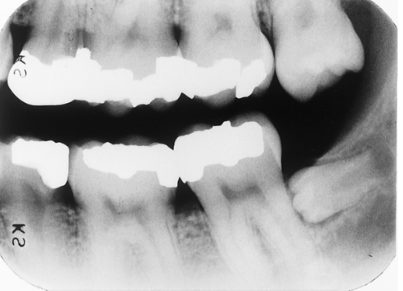

Note the occlusal anatomy of the occlusal surface of the mandibular 2nd molar that has just erupted. Now look at the maxillary 2nd premolar and lower premolars. What is your assessment of these teeth?

enamel hypoplasia

rampant caries

dentin dysplasia

Don't look at me, I don't diagnose.